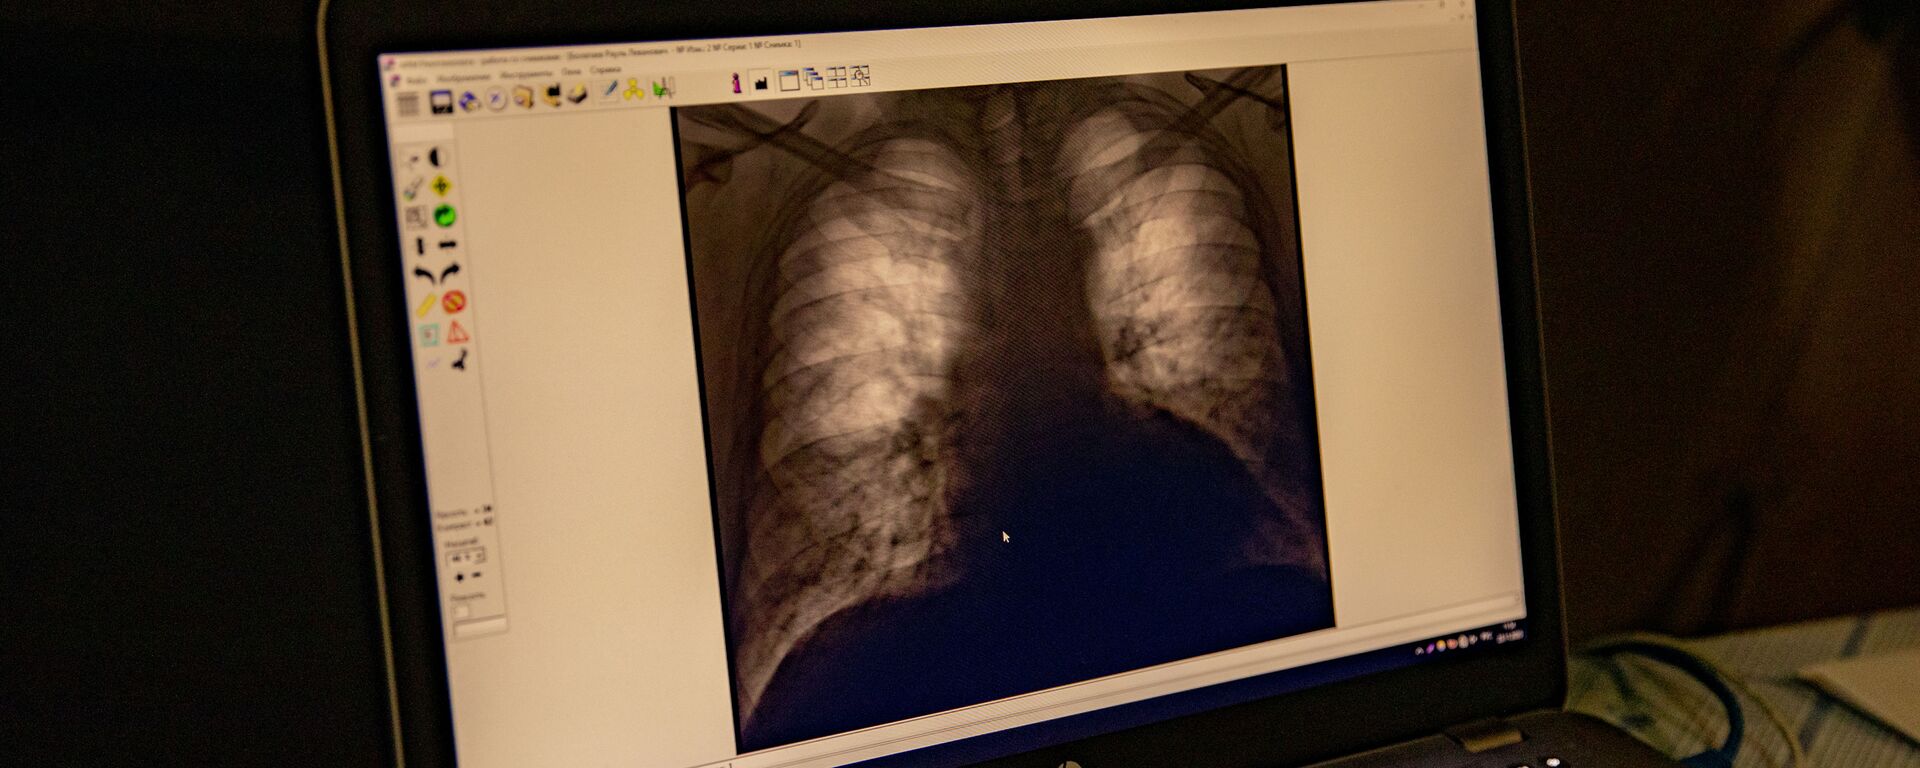

По словам Ванеева, ситуация с туберкулезом в Южной Осетии оценивается как удовлетворительная. В республике ведется планомерная работа по раннему выявлению заболевания, для чего недавно был приобретен новый рентгеновский аппарат.

"Заболевание легче предупредить, чем лечить. Благодаря новому оборудованию становится возможным выявлять туберкулез на ранних стадиях. Важно отметить, что многие жители республики являются гражданами России и нередко проходят лечение в Северной Осетии, а затем возвращаются для долечивания на родину. В этом случае важна преемственность лечения и наличие необходимого запаса препаратов", — подчеркнул специалист.